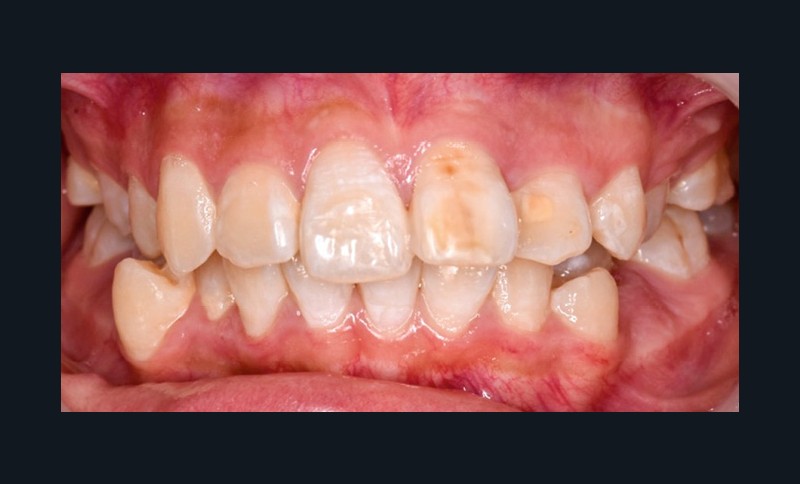

Une patiente âgée de 12 ans se présente en consultation, motivée par la position de son incisive centrale maxillaire, décrite comme « en avant », marquée par une dyschromie et une mobilité de grade 2 selon Muhlemann. L’examen clinique montre l’absence de 23 sur l’arcade, une dysharmonie dents-arcade marquée, un surplomb accentué, et une déviation des milieux inter-incisifs, conséquence du comblement spontané de l’espace de 23. L’ensemble s’inscrit dans un contexte de Classe I d’Angle molaire. L’orthopantomogramme révèle l’inclusion de 23, associée à une résorption radiculaire étendue aux deux tiers de 21. La 22 ne présente aucune altération visible.

La patiente, de profil normodivergent, présente une Classe I squelettique sans troubles fonctionnels (fig. 1-8).